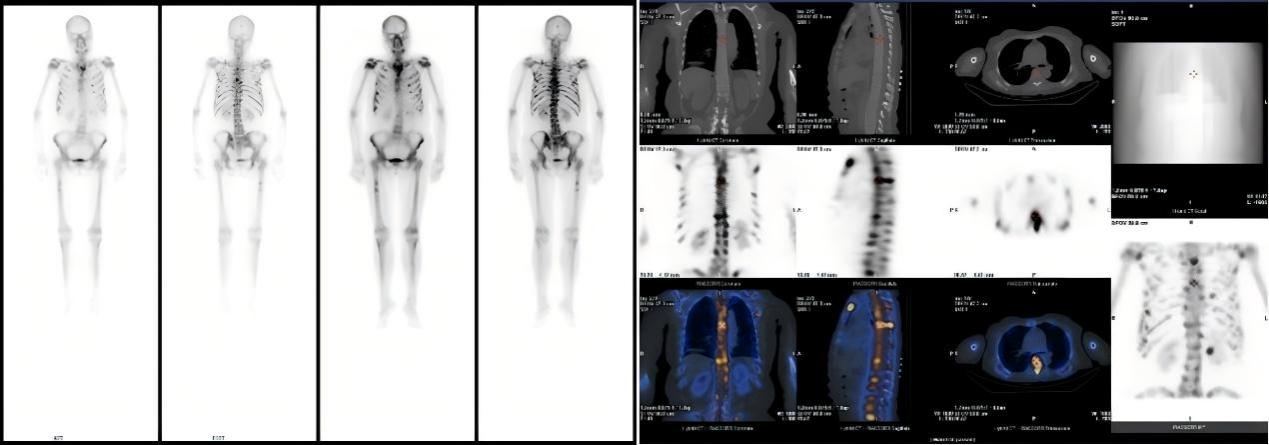

患者因不明原因发热、剧烈骨痛伴体重骤降前来就诊。入院后,全腹及胸部CT未见明显异常,但血常规提示白细胞、淋巴细胞、血小板及红细胞计数均显著降低。为进一步探明病因,临床医生安排了全身骨扫描(SPECT/CT),结果显示全身多处骨骼放射性浓聚,初步怀疑为肿瘤骨转移,其诊疗方向指向实体肿瘤,但其CT却未见明显病灶,诊断陷入了困境。临床医生随即安排可以全身扫描尤其对肿瘤病变尤为敏感的PET-CT检查。

患者全身骨扫描(SPECT/CT)核医学显像图。